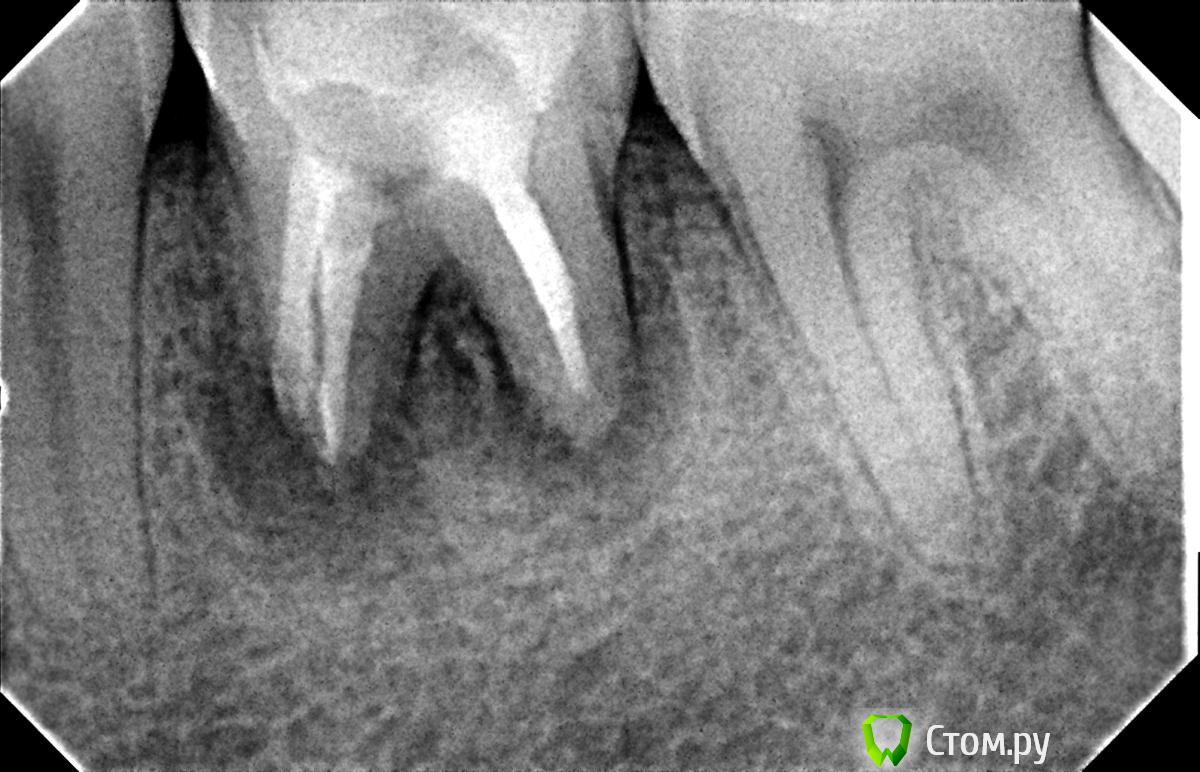

Hans85 Опубликовано 8 января, 2014 Поделиться Опубликовано 8 января, 2014 Только зарегистрировался на форуме,хотелось бы познакомится с коллегами.для начала выкладываю небольшой кейс с названием "Почти мини".Направлен пациент прошло 6 месяцев после фиксации композитной вкладки,заболел.Эндо без рук (только контроль проходимости 10 К-file)Rece+ProFile,пломбирование волна.Всем здравствуйте.P.S Сан Саныч привет)). 12 Ссылка на комментарий

Hans85 Опубликовано 8 января, 2014 Автор Поделиться Опубликовано 8 января, 2014 Привет. Тут ретрит? Логическую цепь картинок выстрой нормально... Первичное эндо Александр Александрович.VTVT техника обработки каналов. Ссылка на комментарий

Hans85 Опубликовано 8 января, 2014 Автор Поделиться Опубликовано 8 января, 2014 НУ еще чуток доступа может кому будет интересноПациент - геморная кариозная полость по дистальной поверхности 47,точка сообщения с полостью зуба обнаружилась,традиционный доступ уничтожил бы зуб,пришлось хитрить. 11 Ссылка на комментарий

Л Ю С Я Опубликовано 9 января, 2014 Поделиться Опубликовано 9 января, 2014 Полагаю на КТ будет не такая уж радужная картинка...Чем завершено лечение? Коронка?что коронку не поставил- плохо, но все признаки хилинга имеются Ссылка на комментарий